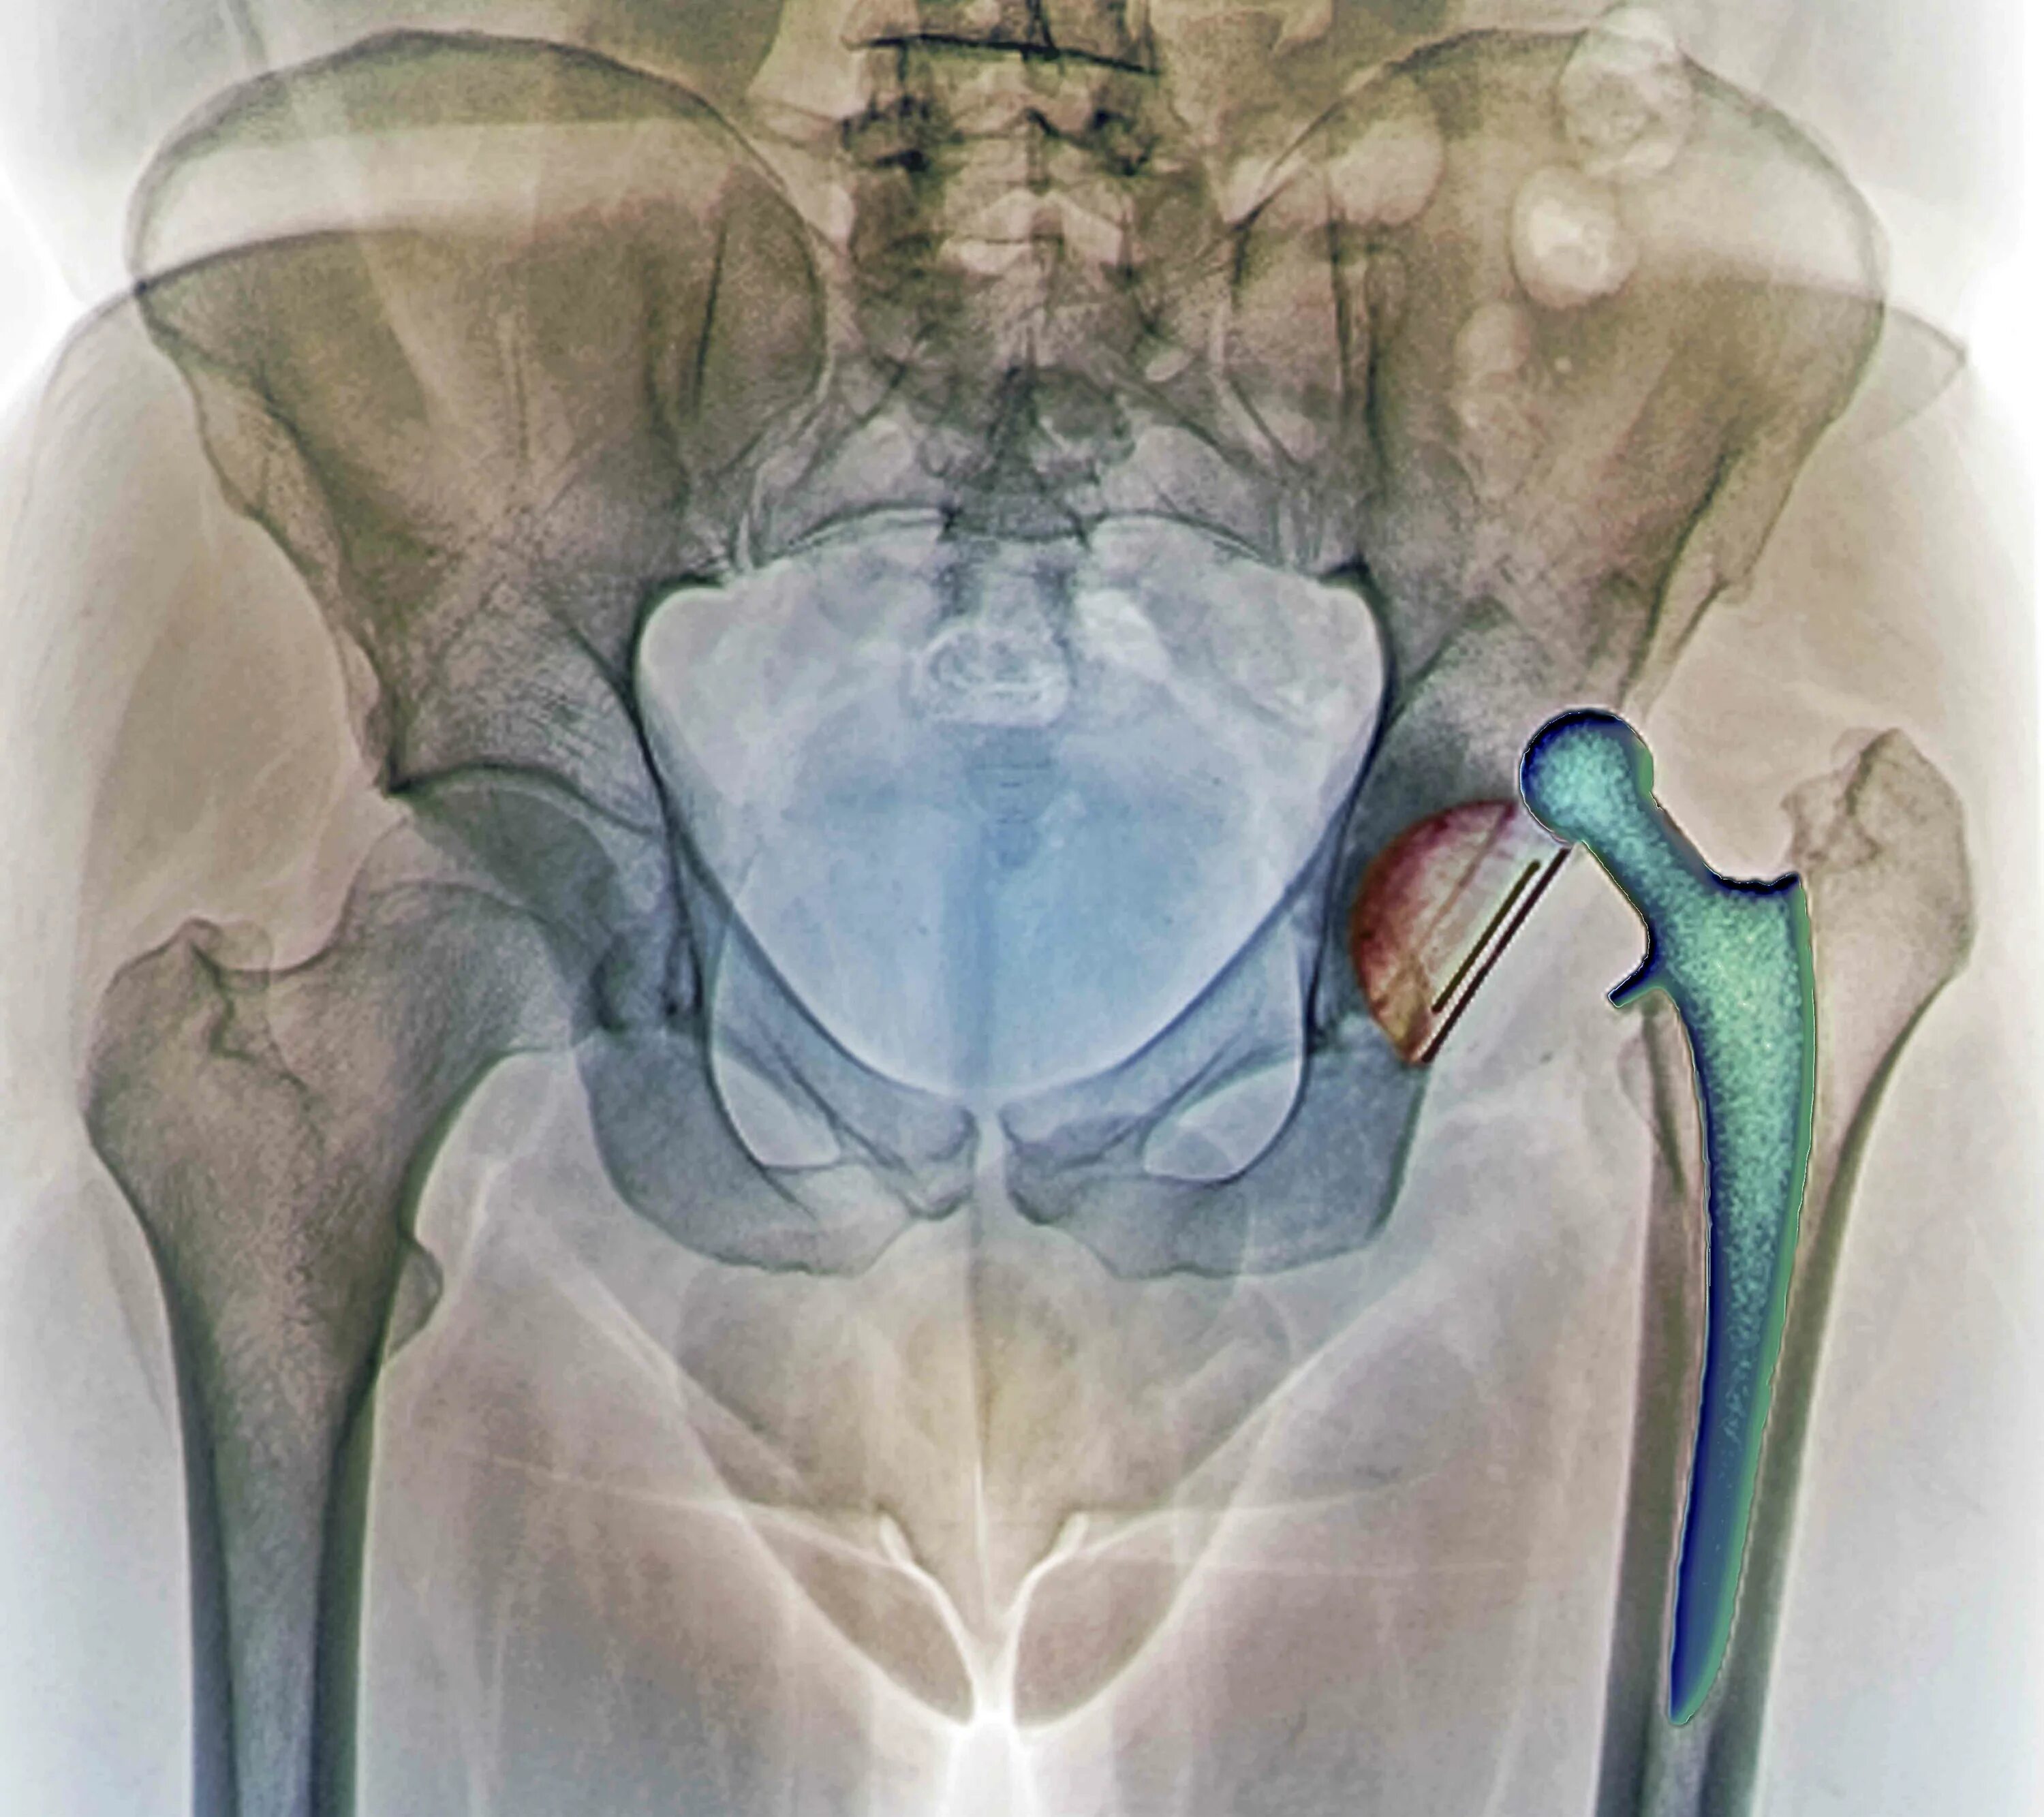

Форум после тазобедренной операции